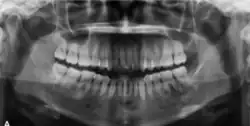

The radiographic features of central ossifying fibroma can be categorised according to the stages.

In its early stages, central ossifying fibroma (COF) appears as a small, well-defined radiolucent lesion due to its fibrous tissue content. Differential diagnoses at this stage include periapical pathology, central giant cell granuloma, and ameloblastoma.[22][23] As the lesion matures, it exhibits a mixed radiolucent-radiopaque appearance due to progressive calcification.[22] At this stage, it should be differentiated from other mixed jaw lesions such as fibrous dysplasia, calcifying epithelial odontogenic tumour, adenomatoid odontogenic tumour, and condensing osteitis.[22] In its mature form, COF may appear predominantly radiopaque, resembling lesions like odontomas, osteoblastomas, or osteosarcomas radiographically.

COF typically presents with well-defined, smooth, and often corticated borders. As a central lesion, it originates within the medullary bone and expands concentrically in all directions.[24] With growth, it may cause tooth displacement, root resorption, inferior displacement of the mandibular canal, and loss or alteration of the lamina dura of adjacent teeth.[25]

In conclusion, COF most commonly occurs in the mandible and expands from a central epicenter. Radiographically, it presents as a well-defined mixed-density lesion,[26] and Cone Beam CT (CBCT) plays a crucial role in its accurate diagnosis and assessment.